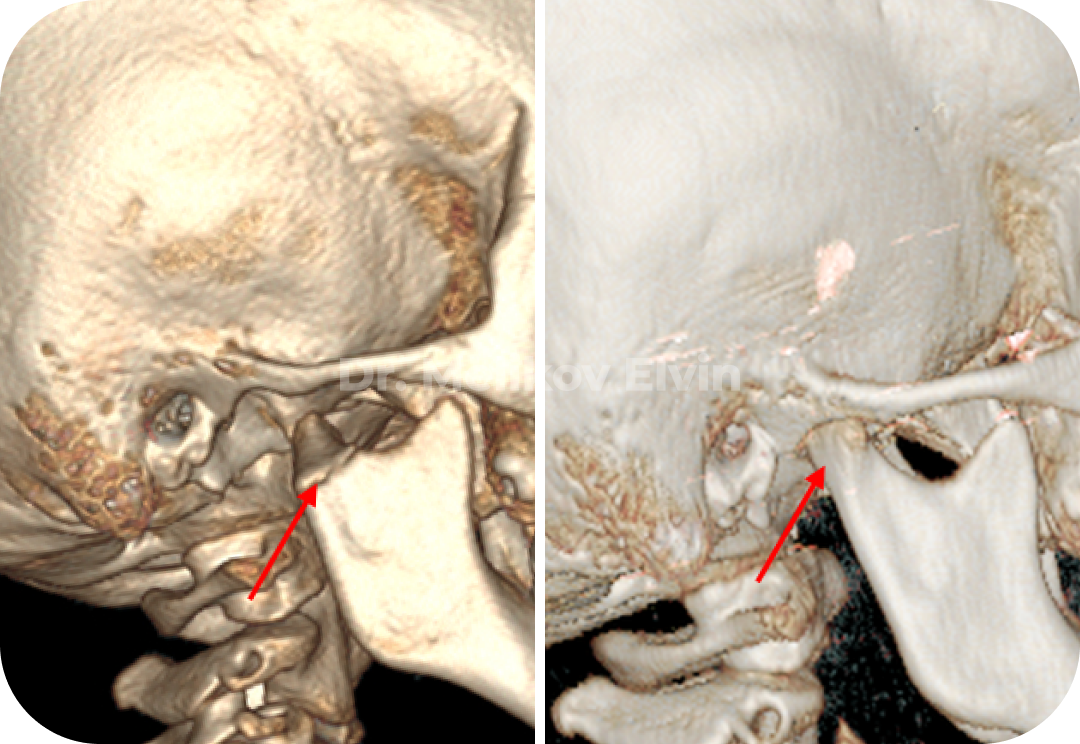

Безоперационное лечение перелома правого мыщелкового отростка нижней челюсти у ребенка 7 лет

🔹Диагноз: Перелом правого мыщелкового отростка нижней челюсти.

🔹Что получили: При дистракции правого внчс, под действием мышц, отросток репонировался и произошла полная консолидация.

Обычно, в таких случаях, предлагают провести хирургическое вмешательство в объеме остеосинтеза мыщелкового отростка. Чтобы добраться к костным структурам, необходимо будет провести разрезы мягких тканей , в том числе и самой капсулы сустава. Не стоит так же забывать, что это ребёнок 7-8 лет, и при такой хирургии нарушаются зоны роста, что впоследствии может стать причиной асимметричный деформации челюстей, а еще хуже необратимых изменений в суставе. Протокол лечения таких детишек оставляет желать лучшего.

На кафедре Детской ЧЛХ Российского университета медицины изготовили специальную окклюзионную пластинку по индивидуальным параметрам, которая дала возможность провести дистракцию в суставе и безоперационно стать причиной реабилитации данного ребёнка. Результат на лицо!